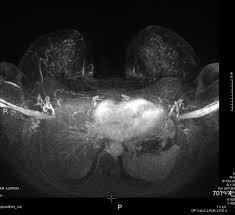

If these tests don't answer the quest. But not every woman who has been diagnosed with breast cancer needs a breast mri. Determining the extent of cancer after a new breast cancer diagnosis. It can also help detect breast cancer in women with breast implants and in younger women who tend to have dense breast tissue. An mri can be used to look for a disease, such as breast cancer. But there are also other reasons to have a breast mri. Inflammatory breast cancer affects breast tissue and can appear unusually dimpled or thick. Breast mri images are combined, using a computer, to create detailed pictures. A waiver of informed consent Mri scan is also used in breast screening for young women who are at higher risk of developing cancer. Dcis on mri may create an area of irregular enhancement of the mri dye into the breast. They're often easy to move around (mobile) and may be tender. A breast mri is a highly effective test.

Breast mri is sometimes used in women who already have been diagnosed with breast cancer, to help measure the size of the cancer, look for other tumors in the breast, and to check for tumors in the opposite breast.

They might be at higher risk due to having family members with cancer or because they have certain gene abnormalities (mutations). By comparison, only 11 out of 48 patients, or 23 percent, with all fatty hilum in place had cancer. Because the dye can affect the kidneys, your doctor may. Unlike traditional forms of breast cancer, inflammatory breast cancers do not develop unusual lumps within the affected breast. Magnetic resonance imaging (mri) of the breast — or breast mri — is a test used to detect breast cancer and other abnormalities in the breast. Mri of breast can help breast cancer diagnosis. When women undergo mris to check for breast cancer, the scans sometimes reveal suspicious masses elsewhere in the body, which can generate a lot of anxiety and require more testing. This means that the test finds a mass or other change that seems to show cancer but it is not cancer. A breast mri is a highly effective test. Palpation of benign breast masses. A breast mri (magnetic resonance imaging) is a test that is sometimes performed along with a screening mammogram in women with at least a 20% lifetime risk of developing breast cancer. You may notice dimpling or pitting, and the skin on your breast. Some benign conditions such as fibrocystic disease can look like cancer.

Patients who had baseline breast mri, mammography, and ultrasound examinations were included in this study; The skin looks like the skin of an orange, and may be discolored with painful and itchy breast. By comparison, only 11 out of 48 patients, or 23 percent, with all fatty hilum in place had cancer. Some benign conditions such as fibrocystic disease can look like cancer. Your doctor may recommend a breast mri for the following:

An mri can help find a disease of the lungs or show tumors (growths) in the chest. But not every woman who has been diagnosed with breast cancer needs a breast mri. The features of a malignant breast condition on mri scan are often to do with the outer irregular borders of a lesion. A rash isn't the only visual symptom of inflammatory breast cancer. Any area that does not look like normal tissue is a possible cause for concern. A breast mri scan might also be used to assess the size of the cancer to check which kind of surgery is possible. They work to destroy the tumor or slow down the growth of cancer cells. This appears most commonly as streaking, known as linear enhancement. On the flip side, there are benign (not cancerous) breast changes which can mimic breast cancer as well. This means that the test finds a mass or other change that seems to show cancer but it is not cancer. Breast mri images are combined, using a computer, to create detailed pictures. What does breast cancer look like on a mammogram? The dye collection in the breast can also look clumpy or appear in a section of the breast, depending on the involvement of dcis.